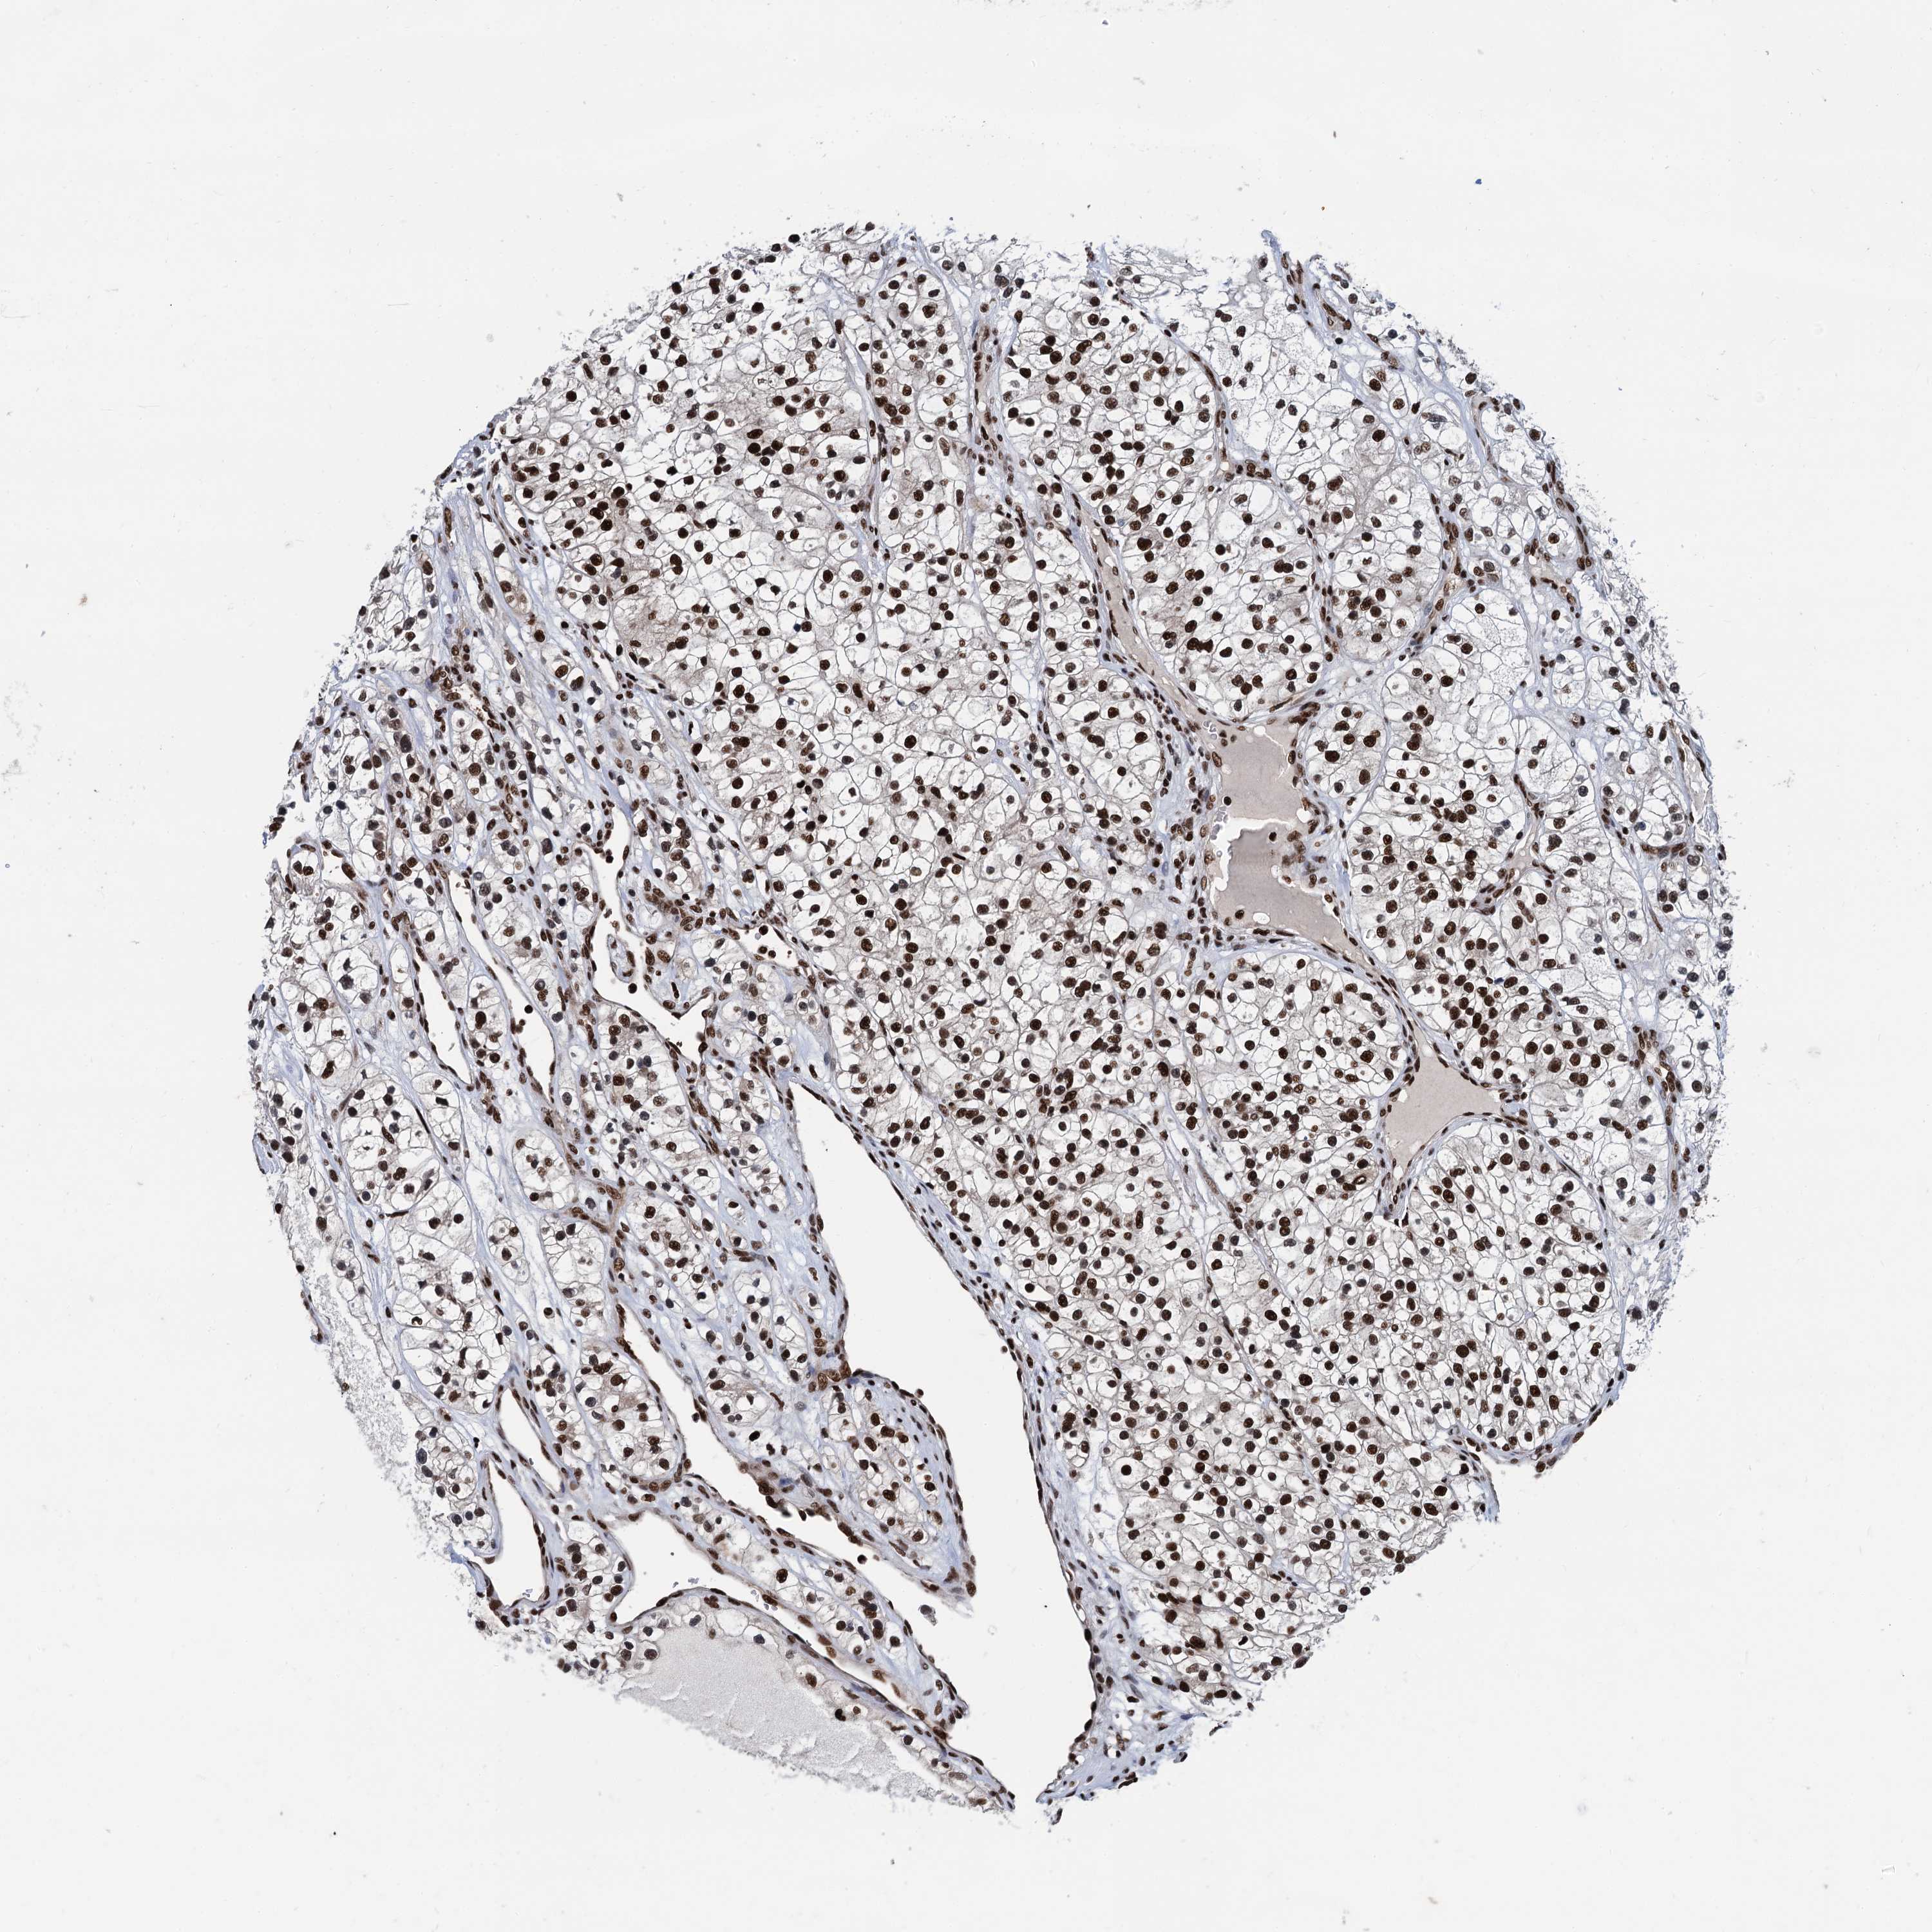

KIDNEY RENAL CLEAR CELL CARCINOMA (VALIDATION) - Interactive survival scatter ploti

The Survival Scatter plot shows the clinical status (i.e. dead or alive) for all individuals in the patient cohort, based on the same data that underlies the corresponding Kaplan-Meier plots. Patients that are alive at last time for follow-up are shown in blue and patients who have died during the study are shown in red.

The x-axis shows the expression levels (FPKM) of the investigated gene in the tumor tissue at the time of diagnosis. The y-axis shows the follow-up time after diagnosis (years). Both axes are complimented with kernel density curves demonstrating the data density over the axes. The top density plot shows the expression levels (FPKM) distribution among dead (red) and alive patients (blue). The right density plot shows the data density of the survived years of dead patients with high and low expression levels respectively, stratified using the cutoff indicated by the vertical dashed line through the Survival Scatter plot. This cutoff is automatically defined based on the FPKM cutoff that minimizes the p-score. The cutoff can be changed by dragging the vertical line or by entering a cutoff value in the square labeled "Current cut-off".

Under the Survival Scatter plot the p-score landscape (black curve; left axis) is shown together with dead median separation (red curve; right axis). Dead median separation is the difference in median mRNA expression between patients who have died with high and low expression, respectively. It is calculated as follows: median FPKM expression of dead patients with high expression - median FPKM expression of dead patients with low expression. This is intended to aid the user in visually exploring custom cutoffs and the associated p-scores and dead median separation.

Individual patient data is displayed and can be filtered by clicking on one or more of the category buttons on the top of the page. Categories describing expression level and patient information include: high, low, alive, dead, female, male and tumor stages. The scale of the x-axis can be toggled between linear and log-scale by clicking on the "x log" button. Mouse-over function shows TCGA ID, patient information and mRNA expression (FPKM) for each patient.

& Survival analysisi

Kaplan-Meier plots summarize results from analysis of correlation between mRNA expression level and patient survival. Patients were divided based on level of expression into one of the two groups "low" (under cut off) or "high" (over cut off). X-axis shows time for survival (years) and y-axis shows the probability of survival, where 1.0 corresponds to 100 percent.

PPP4R1 is not prognostic in Kidney Renal Clear Cell Carcinoma (validation)

Best expression cut offi

Based on the FPKM value of each gene, patients were classified into two groups and association between prognosis (survival) and gene expression (FPKM) was examined. The best expression cut-off refers the FPKM value that yields maximal difference with regard to survival between the two groups at the lowest log-rank P-value. Best expression cut-off was selected based on survival analysis .

When clicking on this number, the vertical dashed line indicating cut-off, the interactive survival plot, and the Kaplan-Meier curve will be adjusted to show results based on the best expression cut-off.

: 24.11

P scorei

Log-rank P value for Kaplan-Meier plot showing results from analysis of correlation between mRNA expression level and patient survival.

N/A

TCGA RNA samplesi

RNA-seq data is reported as average FPKM (number Fragments Per Kilobase of exon per Million reads), generated by the The Cancer Genome Atlas (TCGA) .

Normal distribution across the dataset is visualized with box plots, shown as median and 25th and 75th percentiles. Points are displayed as outliers if they are above or below 1.5 times the interquartile range. FPKM values of the individual samples are presented next to the box plot.

Average pTPM 29.0

Number of samples 100